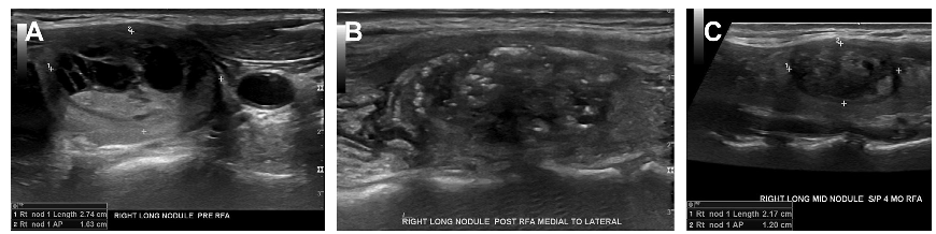

Radiofrequency Ablation

Radiofrequency Ablation: Right sided nodule (A) before RFA (B) immediately post-RFA demonstrating classic ultrasonographic changes (C) 4- months post – RFA demonstrating clinically significant volume reduction.